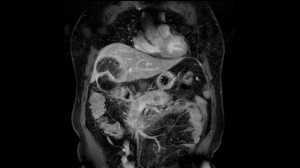

Resonancia magnética de abdomen es un examen de imagen que utiliza imanes y ondas de radio potentes para crear imágenes del interior del área abdominal. No emplea radiación (rayos X). Las imágenes por resonancia magnética solas se denominan cortes y se pueden almacenar en una computadora o imprimir en una película. Un examen produce docenas o algunas veces cientos de imágenes.

Una resonancia magnética del abdomen proporciona imágenes detalladas del área ventral desde muchos planos. Con frecuencia, se utiliza para clarificar hallazgos de radiografías o tomografías computarizadas previas.

• La causa de hinchazón o dolor abdominal

• La causa de resultados anormales en exámenes de sangre, como problemas renales o hepáticos

Una resonancia magnética puede diferenciar tumores de tejidos normales. Esto puede ayudarle al médico a conocer más acerca del tumor, como el tamaño, la gravedad y la propagación, lo cual se denomina estadificación.